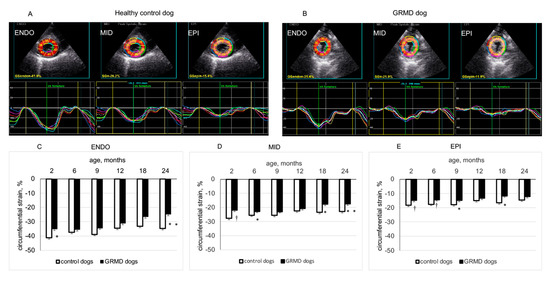

3.2. Changes in CS in the Three LV Wall Layers Analyzed by 2D-STE from the Three Short-Axis Views in GRMD and Healthy Control Dogs through Time

| Apical endocardial CS | Control | −41.2 ± 2.7 | −37.4 ± 2.1 | −38.8 ± 4.5 | −34.5 ± 0.8 | −33.2 ± 1.7 | −34.7 ± 2.3 | 0.2656 | 0.0031 |

| GRMD | −35.1 ± 1.4 * | −35.5 ± 1.1 | −34.4 ± 1.4 | −31.1 ± 1.1 | −26.5 ± 2.1 | −24.8 ± 2.0 * | <0.0001 | ||

| Apical middle layer CS | Control | −27.7 ± 1.2 | −25.5 ± 1.2 | −25.6 ± 2.2 | −22.5 ± 0.7 | −23.4 ± 0.8 | −22.9 ± 1.1 | 0.0626 | 0.0004 |

| GRMD | −21.9 ± 0.6 † | −22.8 ± 0.5 * | −22.9 ± 0.9 | −20.7 ± 0.6 | −17.7 ± 1.3 † | −17.4 ± 1.3 † | <0.0001 | ||

| Apical epicardial CS | Control | −18.2 ± 0.9 | −17.6 ± 1.1 | −18.0 ± 1.5 | −15.0 ± 0.1 | −16.5 ± 0.6 | −14.7 ± 0.7 | 0.0881 | 0.0025 |

| GRMD | −14.8 ± 0.6 † | −14.3 ± 0.4 † | −14.8 ± 0.6 * | −13.3 ± 0.7 | −11.7 ± 1.0 * | −12.2 ± 0.9 | 0.0054 | ||

| Mid−chamber endocardial CS | Control | −37.3 ± 0.8 | −31.9 ± 1.1 | −30.9 ± 1.1 | −32.2 ± 3.0 | −29.8 ± 1.3 | −31.9 ± 2.6 | 0.0068 | 0.1544 |

| GRMD | −33.2 ± 0.7 † | −33.0 ± 0.8 | −31.9 ± 1.2 | −30.7 ± 1.2 | −25.9 ± 1.8 | −22.9 ± 1.9 * | <0.0001 | ||

| Mid−chamber middle layer CS | Control | −24.7 ± 0.8 | −23.0 ± 0.9 | −23.1 ± 0.8 | −22.6 ± 1.2 | −22.0 ± 0.8 | −23.8 ± 1.3 | 0.2885 | 0.1028 |

| GRMD | −23.7 ± 0.5 | −22.6 ± 0.5 | −22.4 ± 0.9 | −21.5 ± 0.7 | −18.1 ± 0.7 † | −16.5 ± 0.8 † | <0.0001 | ||

| Mid−chamber epicardial CS | Control | −15.7 ± 1.0 | −16.7 ± 0.9 | −17.3 ± 1.0 | −15.5 ± 0.0 | −16.4 ± 0.9 | −18.2 ± 0.6 | 0.3164 | 0.1393 |

| GRMD | −16.5 ± 0.5 | −15.1 ± 0.5 | −15.8 ± 0.8 | −14.6 ± 0.6 | −12.4 ± 0.5 † | −11.7 ± 0.5 † | <0.0001 | ||

| Basal endocardial CS | Control | −32.7 ± 1.5 | −30.4 ± 1.0 | −32.2 ± 1.5 | −30.3 ± 2.5 | −26.0 ± 1.7 | −27.1 ± 1.6 | 0.0216 | 0.0406 |

| GRMD | −32.7 ± 0.9 | −31.8 ± 1.1 | −31.1 ± 1.5 | −27.5 ± 1.4 | −25.9 ± 1.5 | −21.9 ± 1.3 * | <0.0001 | ||

| Basal middle layer CS | control | −23.1 ± 1.0 | −21.8 ± 0.5 | −24.2 ± 1.2 | −22.6 ± 1.1 | −20.6 ± 1.0 | −19.8 ± 1.3 | 0.0383 | 0.0069 |

| GRMD | −23.0 ± 0.6 | −22.5 ± 0.7 | −22.0 ± 1.0 | −21.0 ± 1.0 | −18.1 ± 1.2 | −17.0 ± 1.4 * | <0.0001 | ||

| Basal epicardial CS | Control | −16.7 ± 1.1 | −15.6 ± 0.4 | −18.4 ± 1.2 | −16.7 ± 0.5 | −17.0 ± 0.7 | −14.6 ± 1.6 | 0.1231 | 0.0023 |

| GRMD | −16.2 ± 0.6 | −16.0 ± 0.6 | −15.2 ± 0.7 * | −16.5 ± 0.9 | −13.1 ± 0.8 † | −13.6 ± 0.8 * | 0.0139 | ||